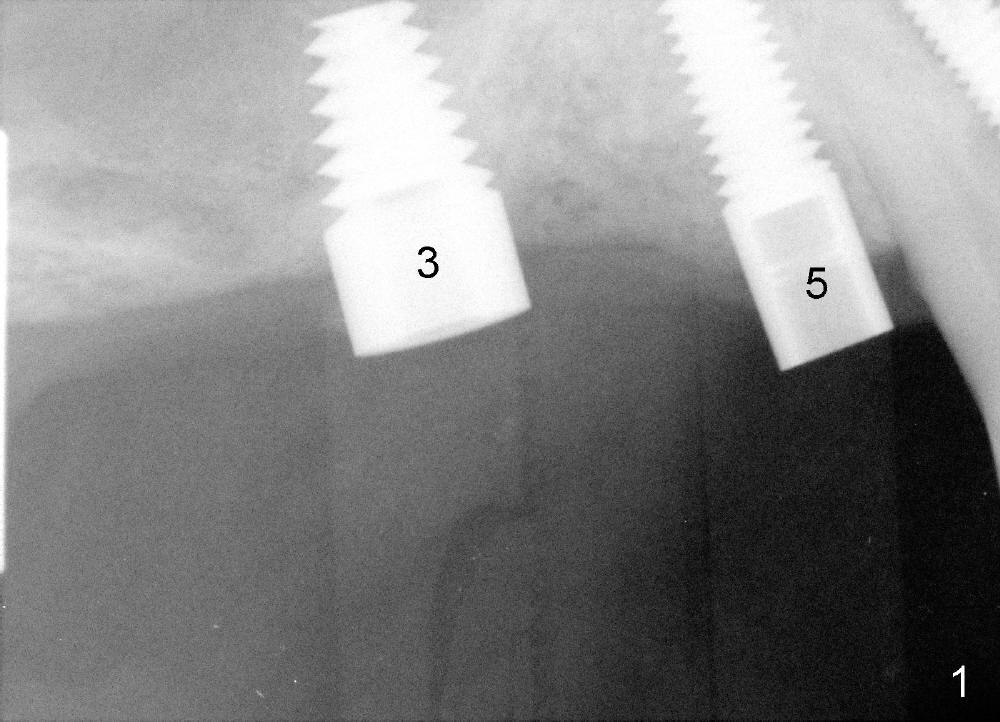

Implants at the site of #3 and 5 were placed for Kent a month earlier.  Immediately before placing a third one in between, something had been done for the first two implants in preparation for guidance.  Can you guess what that is?

Good thinking.  Post guides (0 degree) can be inserted to the wells of the implants after healing screws are removed. Pay attention to special terms assigned by implant companies.